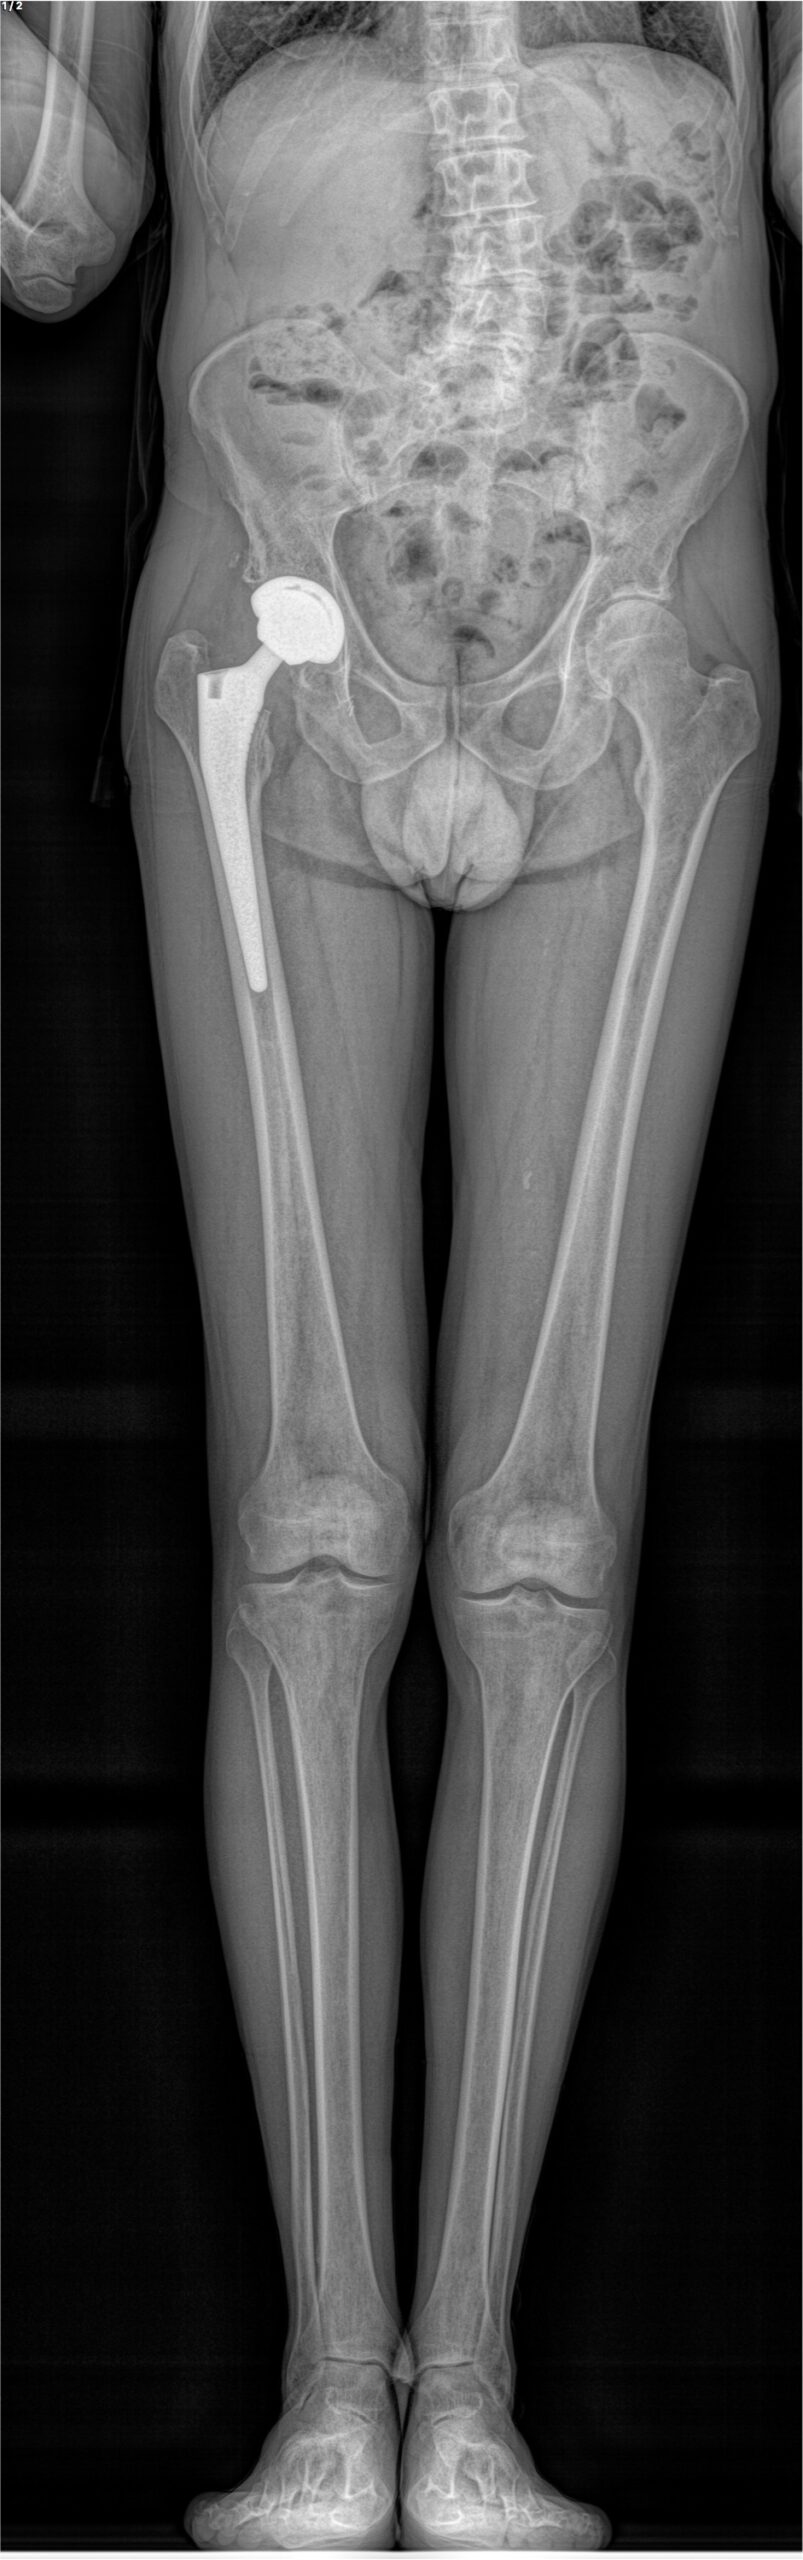

Ce système permet la réalisation de radiographies du corps entier en position debout, en une seule acquisition, sans assemblage d’images et sans distorsion verticale. Des clichés numériques de face et de profil, de tout ou partie du corps, sont obtenus simultanément avec une qualité d’image exceptionnelle et sans aucun agrandissement, garantissant une fiabilité parfaite des mesures.

À la manière d’une photocopieuse, un très fin faisceau de rayons X balaye le corps du patient de la tête aux pieds, réalisant une image de face et une de profil en quelques secondes et de manière simultanée. L’extrême sensibilité des détecteurs développés par Georges Charpak permet cette acquisition corps entier avec une dose de radiation 9 fois inférieure à celle des méthodes radiologiques classiques et jusqu’à 100 fois inférieure à celle d’un scanner.